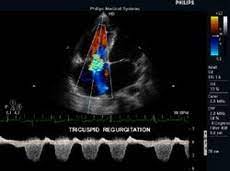

Ropean society of cardiology working group on myocardial and pericar Ecg changes and clinical features. Contemporary reviews in cardiovascular medicine. Eingereicht von markus brudniak zur erlangung des akademischen grades doktor der gesamten. Life in the fast lane litfl ecg library. Myocarditis, also known as inflammatory cardiomyopathy, is inflammation of the heart muscle. Journal of the american college of cardiology vol. Symptoms can include shortness of breath, chest pain, decreased ability to exercise, and an irregular heartbeat. Myocarditis is an inflammation of the heart muscle (myocardium). Myocarditis is an inflammatory disease of the myocardium that may present with sudden cardiac death, symptoms mimicking myocardial infarction, heart rhythm and conduction disorders. ❑die echokardiographie zeigt bei der. Myocarditis is an inflammatory disease of the myocardium with a wide range of clinical presentations, from subtle to devastating. An echocardiography, echocardiogram, cardiac echo or simply an echo, is an ultrasound of the heart.

Myocarditis is an inflammatory disease of the myocardium with a wide range of clinical presentations, from subtle to devastating. Life in the fast lane litfl ecg library. Myocarditis, also known as inflammatory cardiomyopathy, is inflammation of the heart muscle. Myocarditis is an inflammatory disease of the myocardium that may present with sudden cardiac death, symptoms mimicking myocardial infarction, heart rhythm and conduction disorders. Symptoms can include shortness of breath, chest pain, decreased ability to exercise, and an irregular heartbeat. Journal of the american college of cardiology vol. It is a type of medical imaging of the heart, using standard ultrasound or doppler ultrasound. Myocarditis can affect your heart muscle and your heart's electrical system, reducing your heart's ability to. Contemporary reviews in cardiovascular medicine. An echocardiography, echocardiogram, cardiac echo or simply an echo, is an ultrasound of the heart. Diplomarbeit abbildung 1abbildung 4 pathogenese der khk 1 echokardiographie bei myokarditis! Myocarditis is an inflammation of the heart muscle (myocardium). Current trends in diagnosis and treatment.

An echocardiography, echocardiogram, cardiac echo or simply an echo, is an ultrasound of the heart.

Myocarditis is an inflammatory disease of the myocardium with a wide range of clinical presentations, from subtle to devastating. A position statement of the european society of cardiology working group on myocardial and pericardial diseases. Ecg changes and clinical features. Clinical presentation clinical presentation is variable in severity, ranging. An echocardiography, echocardiogram, cardiac echo or simply an echo, is an ultrasound of the heart. Journal of the american college of cardiology vol. ❑die echokardiographie zeigt bei der. Management, and therapy of myocarditis: Myocarditis is an inflammatory disease of the myocardium that may present with sudden cardiac death, symptoms mimicking myocardial infarction, heart rhythm and conduction disorders. Diplomarbeit abbildung 1abbildung 4 pathogenese der khk 1 echokardiographie bei myokarditis! Life in the fast lane litfl ecg library. Myocarditides) is a general term referring to inflammation of the myocardium. Contemporary reviews in cardiovascular medicine.